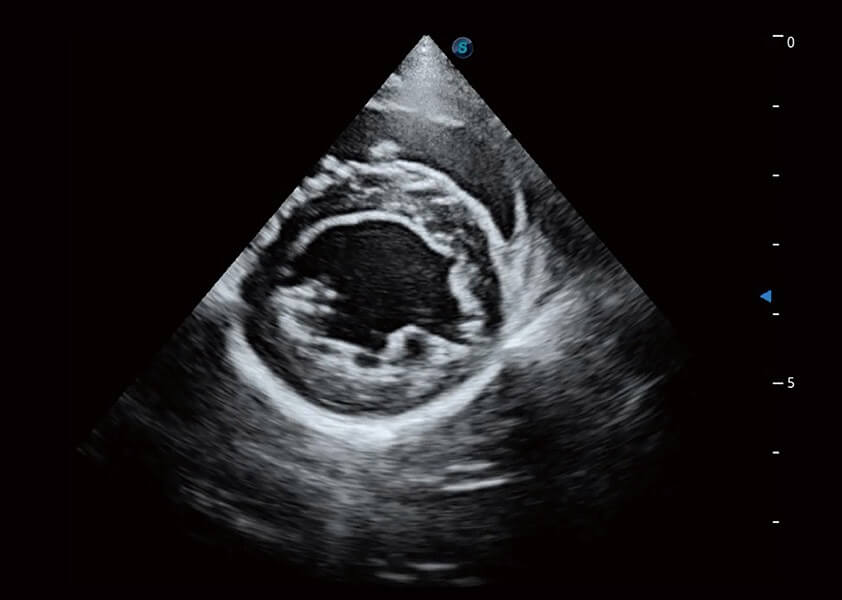

ProPet 60 作為一款高端臺(tái)式動(dòng)物超聲設(shè)備,為動(dòng)物醫(yī)生的日常診斷提供了一系列貼合動(dòng)物臨床需求、解決臨床實(shí)際問(wèn)題的高級(jí)成像功能。憑借全系列高清探頭,滿足醫(yī)生對(duì)腹部、心臟、生殖、淺表、肌骨等成像的所有需求,切實(shí)幫助您提升檢查效率,提高診斷信心。